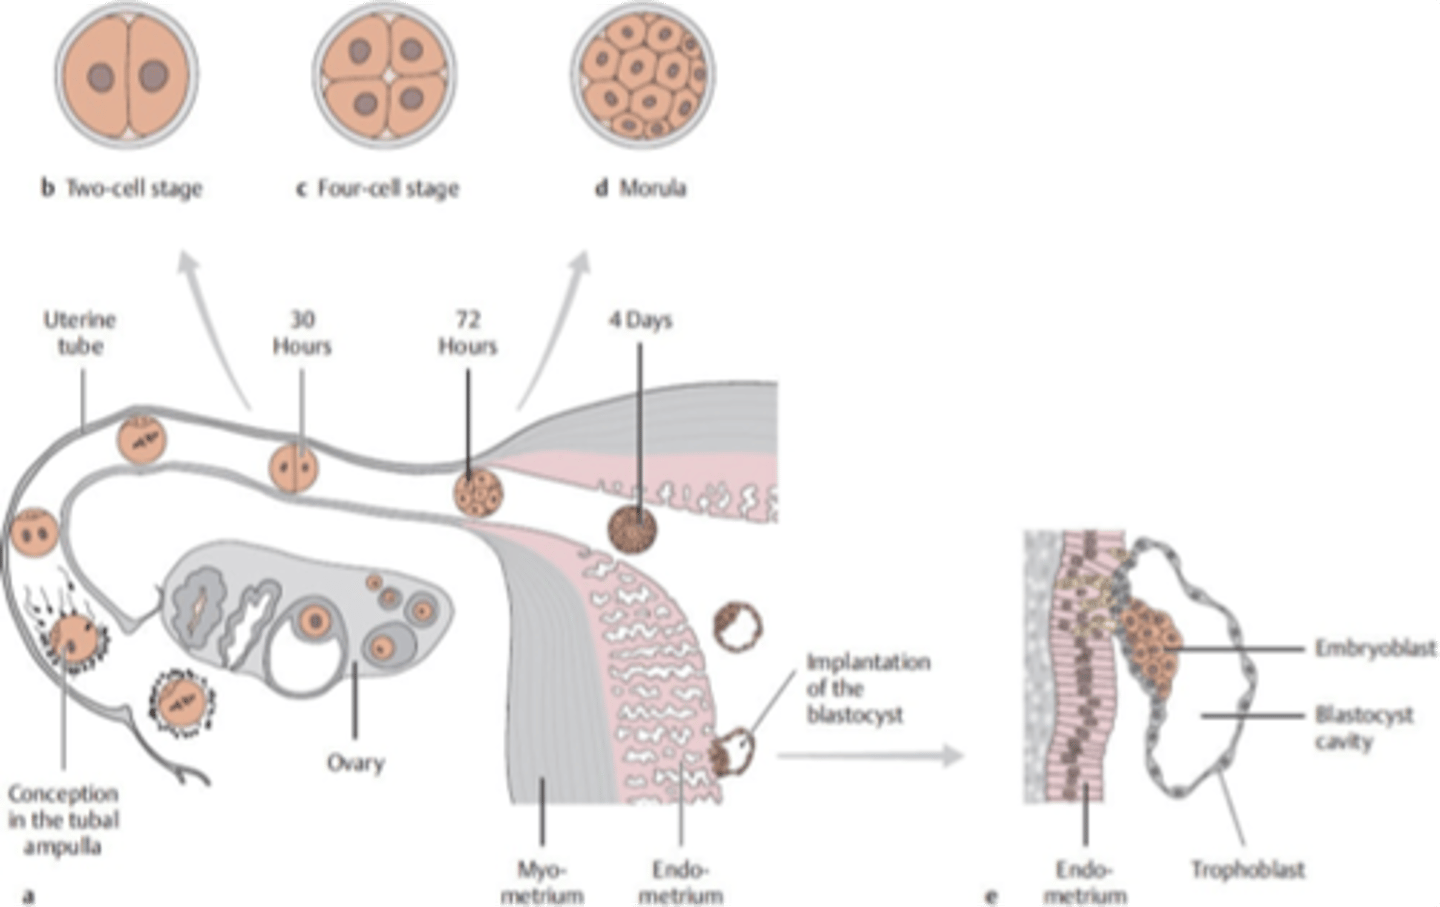

when a zygote undergoes a series of mitotic divisions, this leads to a 16-cell called the __________. as the cell enters the uterus, a cavity begins to appear and leads to the formation of the ___________.

morula, blastocyst

the (morula/blastocyst/gastrula) will form an inner cell mass called the ____________ and an outer cell mass called the ___________

blastocyst

embryoblast (embryo proper)

trophoblast (contributes to placenta)

the inner cell mass of the blastocyst will differentiate into the __________ and _____________ which forms a __________ disc

hypoblast, epiblast, bilaminar